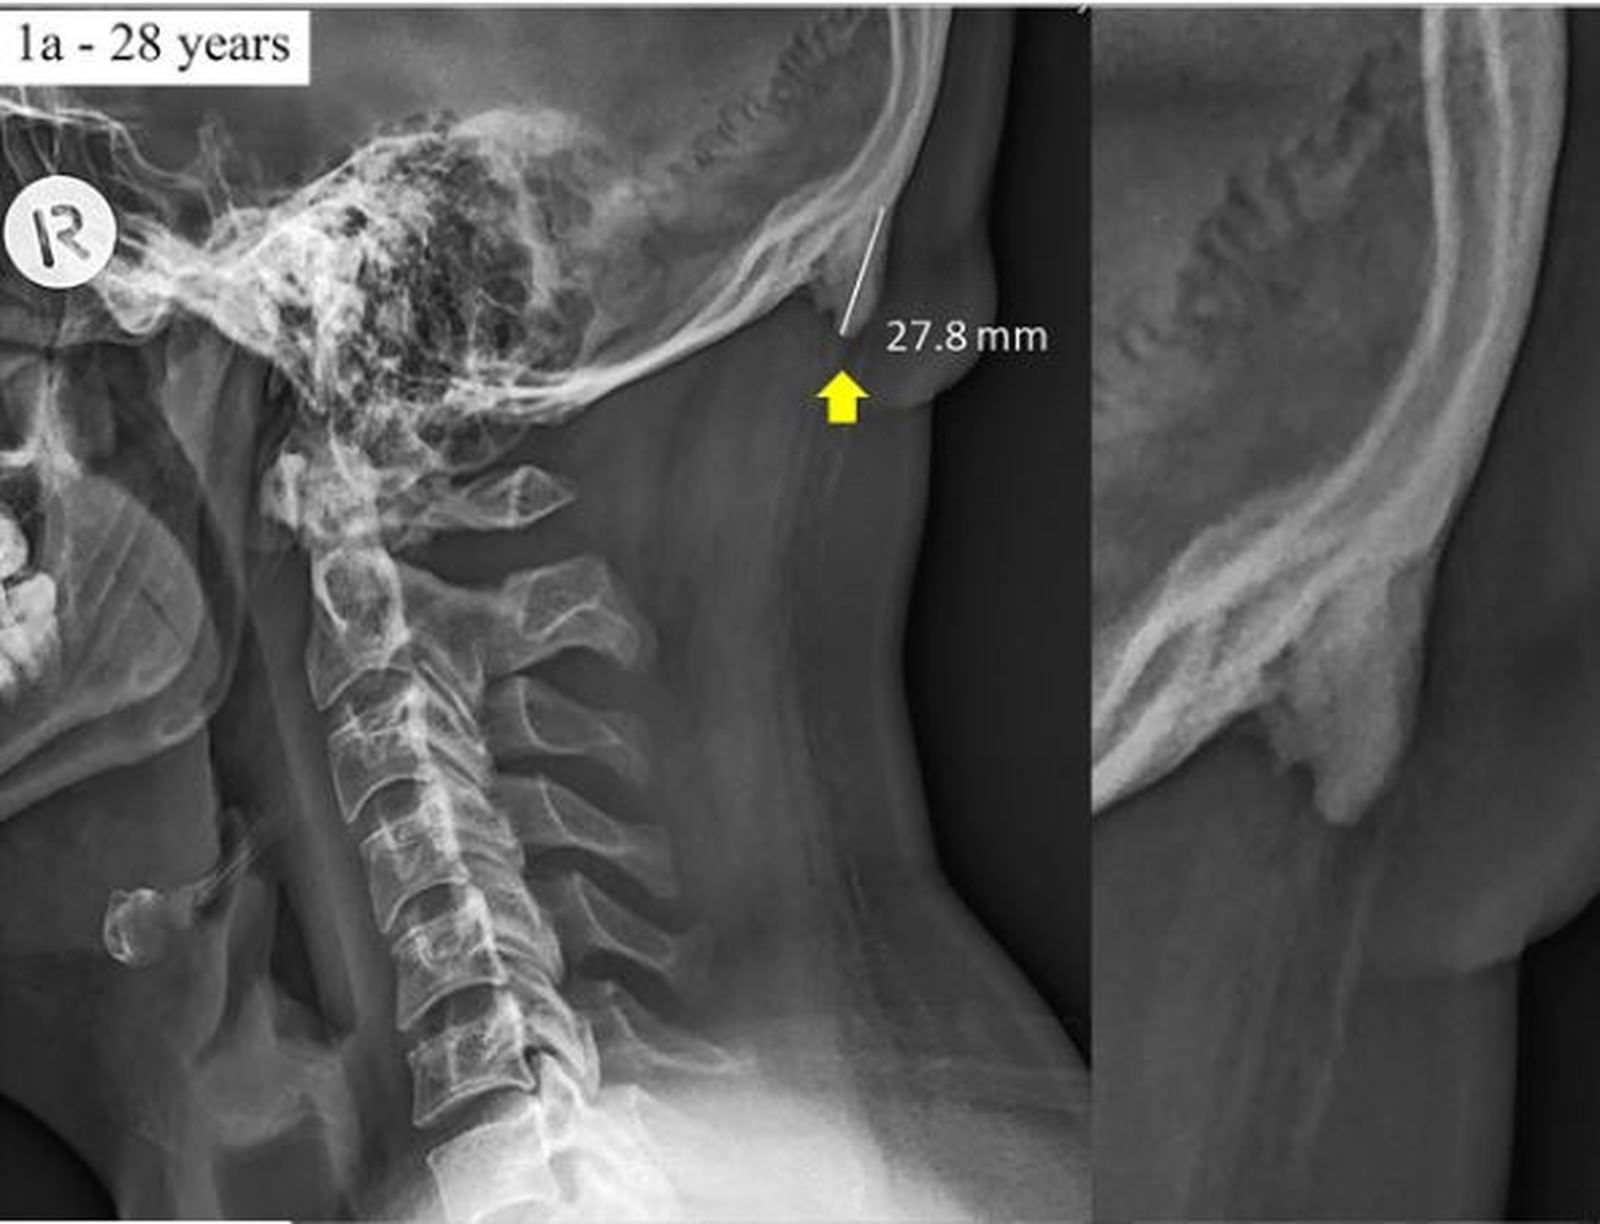

chifre-no-cranioUma pesquisa de uma dupla de cientistas australianos aponta que jovens que ficam muito tempo com a cabeça dobrada para baixo, em uma posição comum para olhar a tela do celular, podem desenvolver uma protuberância na parte de trás do crânio.

O crescimento é comparável a um calo, e fica na parte de trás, na junção entre o crânio e o pescoço. Os pesquisadores são David Shahar e Mark Sayers, da Universidade de Sunshine Coast, em Queensland, na Austrália. Na mídia da Austrália, a pesquisa tem sido noticiada como o desenvolvimento de um chifre na parte de trás do crânio desenvolvido por causa do celular. Shahar e Sayers afirmam que a prevalência dessa protuberância em jovens adultos aponta para uma mudança na postura das pessoas que foi causada pelo uso de tecnologia.